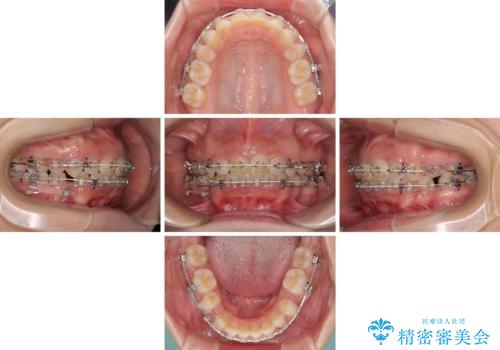

口がしっかりと閉じられない ワイヤー装置での抜歯矯正で出っ歯を改善

- 口元の突出感と口の閉じにくさを気にして来院された患者様です。

上下左右の小臼歯4本を抜歯し、ワイヤー装置にて口元を引っ込めるよう矯正治療を行うこととしました。

上下顎ともに前突しており、特に上顎は著しい突出感でした。

また、下顎歯列には左右差があり、非対称な抜歯が必要と判断されたため、治療は困難なものとなりました。